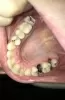

Мне 21 год, вот такие проблемы с зубами, все очень запущенно.

Подскажите, что делать с гнилыми? Я их давно уже не чувствую, если удалить, то как именно? И хочется узнать примерный план действий и стоимость.

Не так все страшно, как Вы расписали. Справа зубы необходимо удалить и поставить имплантаты. С левой стороны зубы необходимо восстановить.